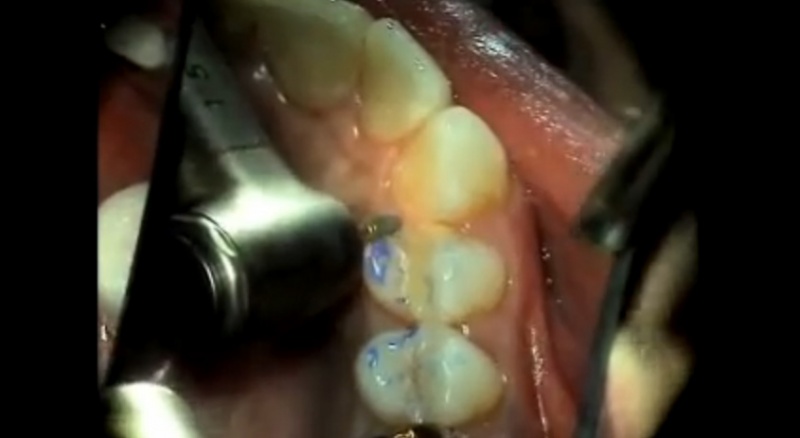

Mastering Occlusal EquilibrationGordon J. Christensen, DDS, MSD, PhD & Valinda Johnston, BS, CDA We are seeing unprecedented levels of cracked natural teeth, TMD, and tooth loss because of occlusal malfunction. Rigid, wear-resi...... |